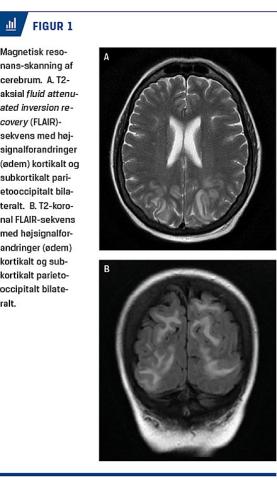

I forbindelse med kramperne blev der registreret normalt blodtryk (129/77 mmHg) og eGFR på 52 ml/min. En akut CT af cerebrum var uden sikre patologiske fund, mens en MR-skanning samme dag viste højsignalforandringer, der sad symmetrisk i occipitallapperne og strakte sig parietalt og frontalt (Figur 1). Forandrin-gerne var forenelige med PRES, og der blev ikke påvist tumorer i hjerneparenkymet. Samme dag måltes meget lavt P-magnesiumniveau på 0,37 mM, og dette blev korrigeret med i.v. givet magnesiuminfusioner, som gentoges de følgende dage pga. vedvarende tendens til hypomagnesiæmi. Det cerebrale ødem blev endvidere søgt behandlet med infusion af mannitol, loopdiuretikum og højdosisprednisolon, hvor sidstnævnte blev givet over en længere periode. Pga. øget intrakranialt tryk blev der ikke udført lumbalpunktur.

Patienten havde efterfølgende cerebrale symptomer i 14 dage med somnolens i de første dage, afasi i få døgn og herefter konfusion og stupor uden fokale udfald. Hun havde bevaret syn i hele forløbet. En kontrol-MR-skanning af cerebrum 29 dage efter debut af PRES viste fuld regression af tilstanden.